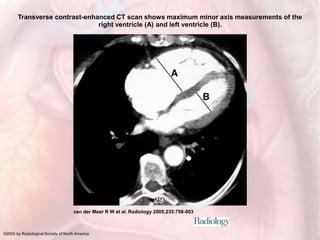

Transverse contrast-enhanced CT scan shows maximum minor axis measurements of the

right ventricle (A) and left ventricle (B).

van der Meer R W et al. Radiology 2005;235:798-803

©2005 by Radiological Society of North America